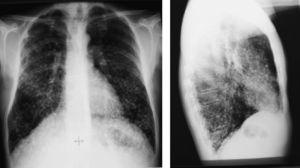

After discussion with the oncological department six months after surgery, palliative chemotherapy with the antiangiogenic drug sorafenib, a tyrosine kinase inhibitor, was decided upon. The patient did not tolerate regular cycles due to the occurrence of hand-foot syndrome. Subsequent controls with chest X-rays (Fig. 3) and CT scans every six months (Fig. 4) showed no nodule changes or decreases in thyroglobulin levels. The last value found on suppressant therapy was 1,921ng/mL with negative antithyroglobulin antibodies.

Only 1–7% of patients with papillary thyroid carcinoma have distant metastases at diagnosis.3 Clinical symptoms of lung involvement are not common. The involvement pattern may range from macronodular to diffuse infiltrates. The latter pattern, when undetected in the chest X-ray, is usually diagnosed using a 123I whole body scan, and may be confirmed with a spiral CT. Almost all patients have high serum thyroglobulin levels despite the fact that lung metastases are not visible in X-rays. In our patient, lung micrometastases were visualized from the start, but were not initially interpreted as such. Clinical records corresponding to the patient's previous stay at the hospital for tuberculosis were requested. Chest X-rays were then reviewed (Figs. 2 and 3) and were seen to be similar to the current X-ray films, taken 23 years later. Thus, the patient already had at that time the metastatic micronodular lung infiltrate, which in the setting of clinical respiratory signs was interpreted as an infectious process, while these new findings suggested, although it could not be categorically stated, that it was a metastatic lung disease of a thyroid origin. The very slow development in this case of a tumor that had remained silent for years should be noted. It should be stressed that the patient had not consulted a specialist during this time.

Figure 2.

Posteroanterior chest X-rays taken in 1988.

Figure 3.

Current chest X-rays.